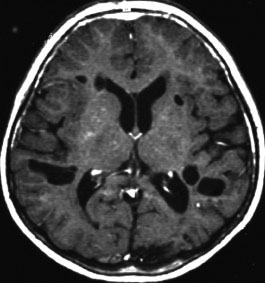

局所照射後の白質変性,脳質壁の白質変性

全脳照射でなくても局所照射でも放射線治療後には白質変性が生じます。無症状のことが多いですが,照射野内の脳萎縮などを伴うと高次脳機能障害などの症状をだすことはあります。

この患者さんは右前頭葉のびまん性星細胞腫に46グレイ23分割という低い線量の局所照射をしました。放射線治療8年後のMRI FLAIR画像です。腫瘍の再燃はなく,脳室周囲の白質が高信号になっています。脳梁や透明中隔の白質組織も高信号になり,非常に軽度の白質変性を示しています。でも,何の症状もありません。注意しなければならないのは,この所見を星細胞腫の再発あるいは進行と捉えて余分な治療をしないようにすることです。とくにグレード2の星細胞腫と乏突起膠腫の時に問題となります。